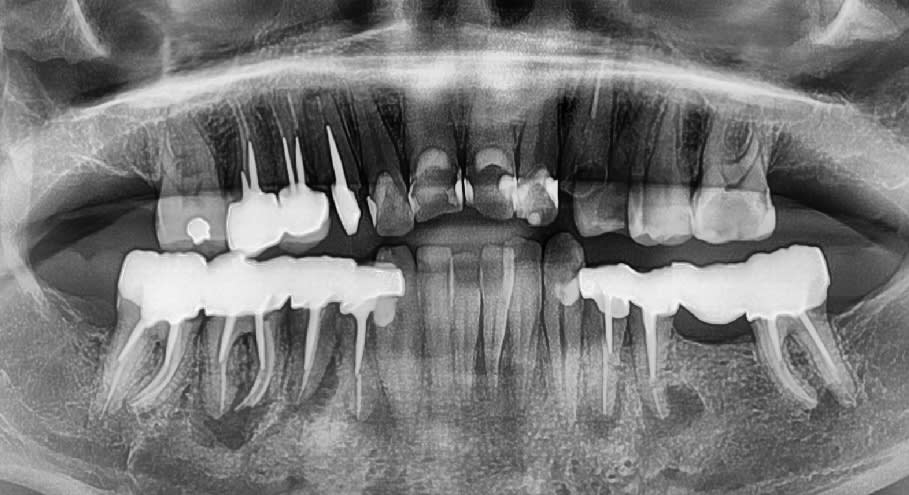

Je vous mets la pano ... avec des surprises . On vire tout , ou presque ?

Je ferais mon maximum pour conserver 33 et 43 pour placer un partiel en bas et un complet en ht.